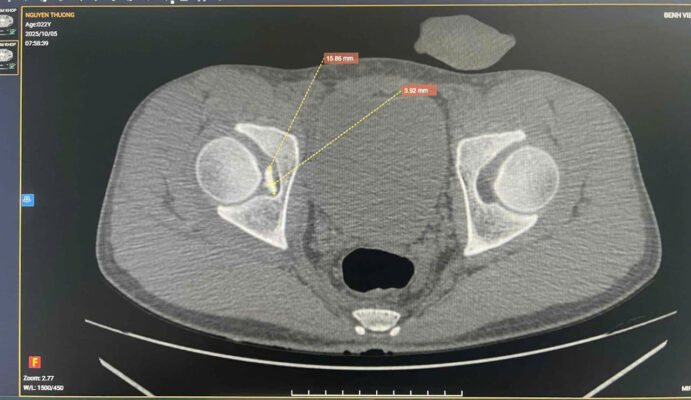

1. MỞ ĐẦU 📚Tổn thương phối hợp giữa dị vật nội khớp háng và mạc giữ bánh chè – đùi trong (Medial Patellofemoral Ligament – MPFL) là tình huống hiếm gặp trong chấn thương chỉnh hình. 👉Các biểu hiện lâm sàng thường không đặc hiệu, dễ bị che lấp bởi triệu chứng đau đa vùng sau chấn thương, dẫn đến nguy cơ bỏ sót tổn thương nội khớp nếu không được đánh giá hình ảnh đầy đủ. 💥Việc phối hợp giữa khám lâm sàng tỉ mỉ và chẩn đoán hình ảnh chuyên sâu (CT, MRI) đóng vai trò quyết định trong việc phát hiện sớm, định hướng điều trị và tiên lượng phục hồi chức năng vận động cho người bệnh. 2. CA LÂM SÀNG 📚 Bệnh nhân nam, sau chấn thương biểu hiện đau vùng háng và gối phải, hạn chế vận động chi dưới cùng bên, đã khám ở BV tuyến trước không xác định được tổn thương. Đêm ngày 03/10, chuyển đến Bệnh viện Quân y 17, qua khám lâm sàng ghi nhận đau sâu vùng háng, đau mặt trong gối khi vận động gấp duỗi, khi sờ ấn, không có biến dạng. 📚Hình ảnh CT scan khớp háng phát hiện một dị vật nhỏ nằm trong ổ khớp háng phải, nghi là mảnh xương vỡ gây kẹt khớp sau chấn thương. MRI khớp gối phải cho thấy tổn thương mạc giữ bánh chè – đùi trong (MPFL) tại chỗ bám vào xương bánh chè, kèm tràn dịch khớp nhẹ. 👉 Nhờ phối hợp chặt chẽ giữa bác sĩ lâm sàng và bác sĩ chẩn đoán hình ảnh, tổn thương phối hợp hiếm gặp này được xác định chính xác, giúp tránh bỏ sót dị vật nội khớp và mô mềm quanh gối khó phát hiện nếu chỉ dựa vào thăm khám. 👉Bệnh nhân được dự kiến lấy dị vật nội khớp háng bằng kỹ thuật ít xâm lấn, nội soi kết hợp màn hình tăng sáng hỗ trợ, bảo tồn mạc giữ khớp bánh chè – đùi trong do không gây di lệch xương bánh chè. 3. BÀN LUẬN 👉 Dị vật nội khớp háng là tổn thương ít gặp, thường thứ phát sau chấn thương gãy xương vùng chậu – ổ cối. Trong khi đó, rách MPFL là tổn thương hay gặp nhất trong trật khớp, gãy xương bánh chè cấp, nhưng hiếm khi xuất hiện đồng thời với dị vật nội khớp háng. Khi hai tổn thương này cùng tồn tại, triệu chứng thường chồng lấp, dễ dẫn đến chẩn đoán không đầy đủ hoặc điều trị chưa triệt để.

✓ Theo Guerrero và cộng sự, MRI là phương tiện hiệu quả nhất để nhận diện tổn thương MPFL và phân loại mức độ rách (tại điểm bám vào bánh chè, tại xương đùi hoặc rách đoạn giữa), trong khi CT giúp phát hiện chính xác các mảnh xương tự do hoặc dị vật trong khớp [3]. ✓ Các tác giả Selmene MA (2022) và Davis ES (2019) cũng khẳng định rằng kỹ thuật lấy dị vật nội khớp háng ít xâm lấn hoặc có hỗ trợ C-arm giúp giảm sang chấn mô mềm và rút ngắn thời gian hồi phục [1],[2]. ✓ Trong báo cáo này, việc phối hợp CT – MRI đã cho phép phát hiện đầy đủ cả hai tổn thương, đồng thời định hướng phẫu thuật hợp lý: lấy dị vật nội khớp nội soi, đồng thời khâu phục hồi cấu trúc mạc giữ khớp bánh chè – đùi trong nếu cần thiết. ✓ Cách tiếp cận này giúp hạn chế nguy cơ bỏ sót tổn thương nhỏ, bảo tồn cấu trúc khớp và phục hồi sớm chức năng vận động. 4. KẾT LUẬN ✓Tổn thương phối hợp giữa dị vật nội khớp háng và rách mạc giữ bánh chè – đùi trong là hiếm gặp và có thể bị bỏ sót nếu không được đánh giá toàn diện. ✓Sự phối hợp chặt chẽ giữa bác sĩ lâm sàng và chẩn đoán hình ảnh là yếu tố then chốt giúp chẩn đoán chính xác, lựa chọn chiến lược điều trị hợp lý, mang lại kết quả phục hồi tối ưu cho người bệnh. 📚Trường hợp tại Bệnh viện Quân y 17 là minh chứng cho năng lực chuyên sâu của đơn vị trong chẩn đoán và xử trí các tổn thương chấn thương chỉnh hình phức tạp, góp phần nâng cao chất lượng điều trị và an toàn người bệnh. 5. TÀI LIỆU THAM KHẢO [1]. Selmene MA, et al. Minimally invasive removal of intra-articular hip fragments. [Journal of Orthopaedic Case Reports]. 2022. [2]. Davis ES, et al. A novel technique to remove posterior intra-articular hip foreign bodies via anterior approach. Tech Orthop. 2019;34(4):302-306. [3]. Guerrero P, Li X, Patel K, Brown M, Busconi BD. Medial patellofemoral ligament injury patterns and associated pathology in lateral patella dislocation: an MRI study. Sports Med Arthrosc Rehabil Ther Technol. 2009;1:17. [4]. Conlan T, Garth WP Jr, Lemons JE. Evaluation of the medial soft tissue restraints of the extensor mechanism of the knee. J Bone Joint Surg Am. 1993;75:682-693. [5]. Nomura E, Inoue M, Osada N. Anatomical analysis of the medial patellofemoral ligament of the knee, especially the femoral attachment. Knee Surg Sports Traumatol Arthrosc. 2005;13:510-515. [6]. Smith A, et al. Medial patellofemoral ligament reconstruction: a systematic review. Orthop J Sports Med. 2024;12(1):1-10.